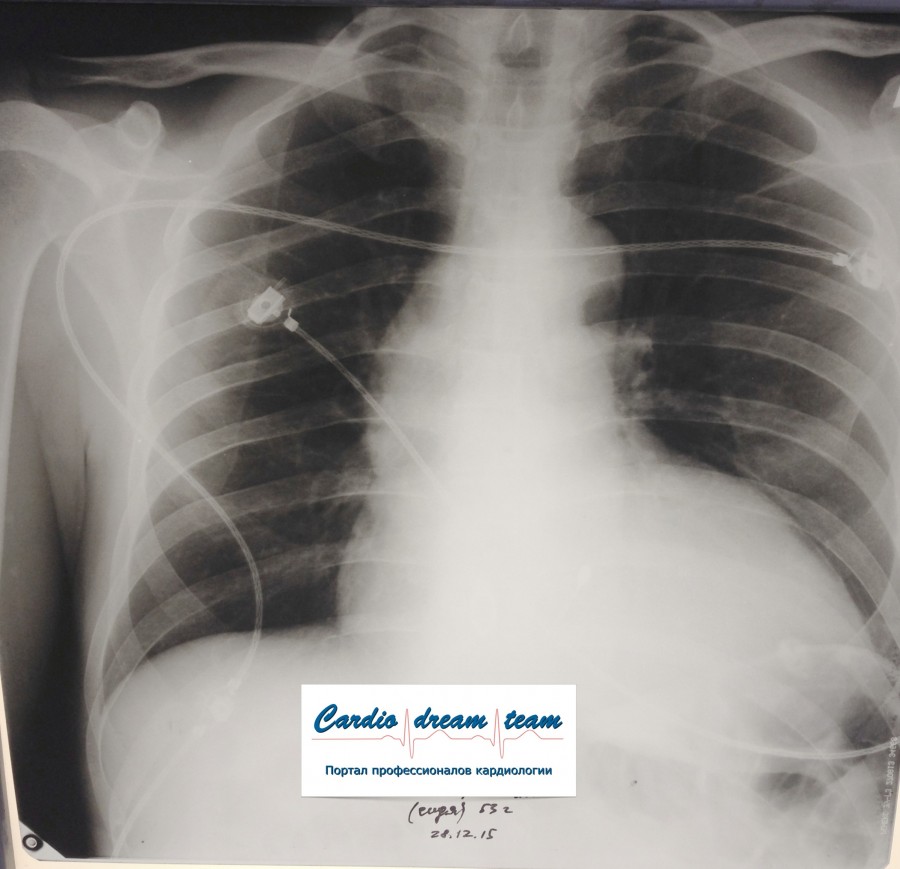

Не обсуждалась Дата 23-ИЮЛ-15 ОПИСАНИЕ: Проведена рентгенография органов грудной клетки в прямой проекции, положение лежа, условия ПИТ Легочные поля: неравномерно прозрачны за счет сосудистого обогащения, в базальных отделах с обеих сторон, отмечается сгущение легочного рисунка, за счет гиповентиляции, в плевральных полостях жидкость Легочный рисунок: Изменен по смешанному типу: обогащен за счет сосудистого компонента, деформирован за счет склероза. Корни: бесструктурны, расширены за счет сосудистого компонента, обогащены Синусы: определяется наличие жидкости по линии 5 ребра Сердце: широко лежит на диафрагме отмечается расширение границ сердечной тени влево, вправо экг-электроды. ЗАКЛЮЧЕНИЕ: Рентген-признаки 2-х стороннего гидроторакса с гиповентиляцией базальных сегментов.. Признаки застоя по МКК 2 степени (умеренно выраженный). Пневмосклероз. Р-признаки гипертрофии левого желудочка сердца. Склероз аорты.